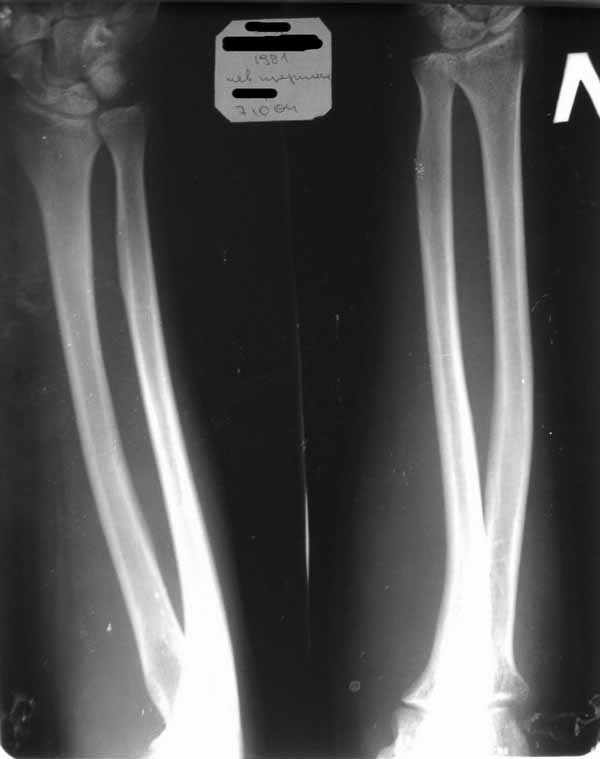

Уважаемые коллеги!Требуется ваша помощь. На консультацию обратился пациент 30 лет с жалобами на ограничение активных движений в левом плечевом суставе. Пассивные – в полном объеме. Со слов – имела место некая родовая травма. К тому же отмечается незначительный дефицит иннервации n.radialis (снижение «силы» разгибателей-сгибателей в кистевом суставе и отведения 1 пальца; неврологи никакого специфичного лечения не назначают). Также имеется контрактура локтевого сустава: сгибание в полном объеме, разгибание 150 градусов, супинация в пределах 7 градусов. Функция конечности в принципе устраивает. Скелетных травм в анамнезе нет. Вопрос: есть ли смысл заниматься какими-либо реконструкциям на плечевом суставе и как можно улучшить функцию скомпрометированных суставов? Заранее всем благодарен

Уважаемый Михаил, у Вашего пациента вероятнее всего "родовая травма" была скелетной, т.е. во время родовспоможения произошел эпифизеолиз дистального эпифиза плечевой кости. Клинически это проявляется некоторым непродолжительным ограничением подвижности в конечности, консолидация (учитывая возраст) проходит достаточно быстро (7-10 дней). Бывает, что при выписке из роддома ребенка уже ничего не беспокоит. Имеющийся на снимке локтевого сустава варус дистального метафиза плеч кости может быть результатом такой травмы. Что касается неврологии, при подобной травме может произойти повреждение лучевого нерва, но это как правило следствие больших смещений эпифиза (заметили бы сразу). Второй вариант - роды столь травматичны, что повредили и плечевое сплетение - проксимальный паралич Эрба, который либо не распознали, либо плохо лечили, в итоге ограничение амплитуды подвижности в плечевом суставе.